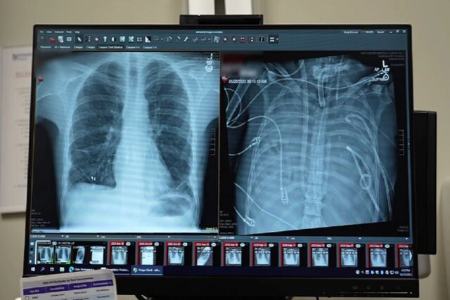

وضعیت تهدیدکننده حیات

قبل از قرار گرفتن روی سیستم ریه مصنوعی، این مرد دچار سندرم حاد دیسترس تنفسی شده بود که یک وضعیت اغلب تهدیدکننده حیات است که در آن ریهها نمیتوانند اکسیژن کافی جذب کنند و این مشکل توسط ویروس آنفلوانزا ایجاد شده بود. سپس او روی ونتیلاتور قرار گرفت، اما دچار عفونت مقاوم به دارو شد. این عفونت باعث شد قسمتهایی از ریههای او پر از چرک شود و او وارد شوک سپتیک شود که در این مرحله قلب و کلیههایش شروع به از کار افتادن کردند.

بهارات میگوید: او خیلی بیمار بود، دچار ایست قلبی شد و در حال مرگ بود. از آنجا که این مرد خیلی بیمار بود که پیوند ریه دریافت کند، گروه پزشکان تصمیم گرفتند ریههای او را که منبع عفونت بود، بردارند.

به طور شگفتانگیز، مرد شروع به بهبود سریع کرد. در عرض ۴۸ ساعت، او همه داروها برای حمایت از فشار خون را کنار گذاشت، عملکرد کلیه او کاملا بازیابی شد و قلب او به طور طبیعی کار میکرد. در این مرحله، مرد پیوند دو ریه را دریافت کرد و سالها بعد هیچ نشانهای از رد عضو یا اختلال عملکرد ریه نشان نداد. اکنون تقریبا سه سال از انجام این کار گذشته است و حال بیمار واقعا خوب است.